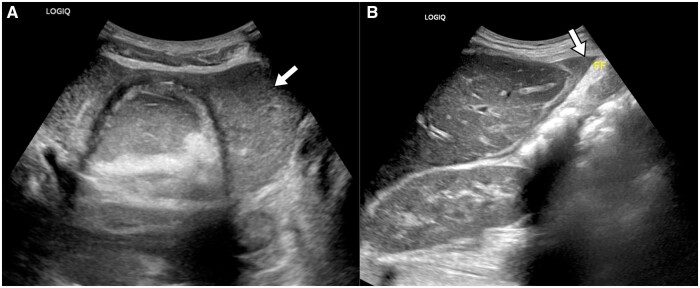

Spontaneous rupture of ovarian dermoid cysts is uncommon. We describe a case of a 32-year-old female who presented to the emergency room with abdominal pain and distension. The patient was discovered to have a ruptured dermoid cyst which caused chemical peritonitis and was managed surgically.